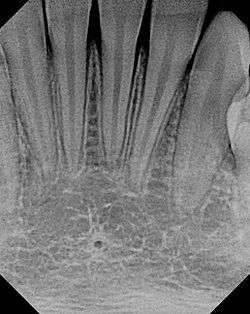

The small lingual foramen (black "hole" in lower portion of picture) as seen on a periapical radiograph of the anterior mandible.

The lingual foramen is a small opening situated on the lingual (tongue) side surface of the anterior mandible through which small blood vessels pass.The lingual foramen is usually situated in the midline of the internal surface of the mandible at the level of or superior to the mental spines.[1]